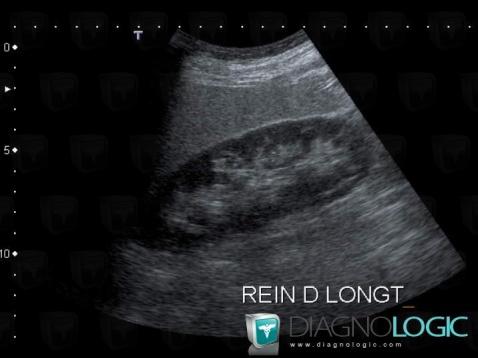

Here is the specific information in the key image above:

- Diagnosis Fatty infiltration, Location(s) Liver, with gamuts Hyperechoic liver